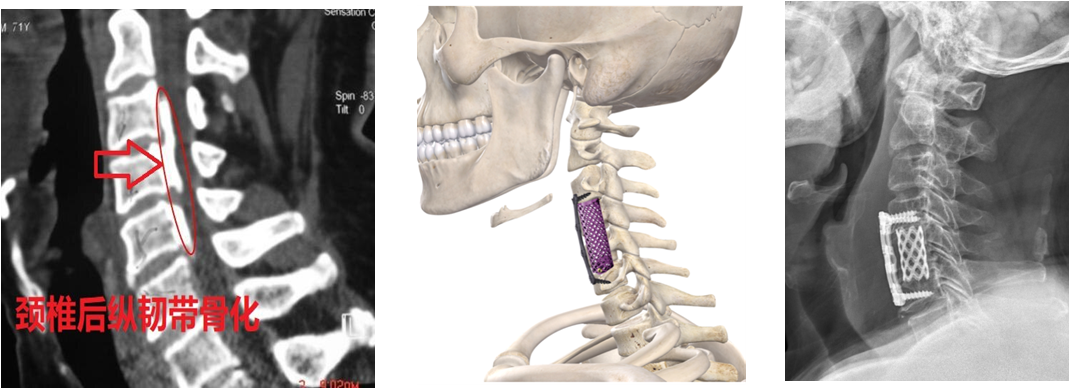

颈椎后纵韧带骨化(OPLL)因发病率高、累及的位置高、对病人危害大和手术难度高风险大,成为手术失败的“重灾区“。颈椎OPLL简单来说是指因颈椎的后纵韧带发生骨化,随着骨化生长和进展逐渐出现压迫脊髓和神经,从而产生感觉运动功能障碍以及植物神经功能紊乱的一种疾病,此病病因不明,目前认为多与基因遗传、代谢障碍和慢性损伤有关。颈椎OPLL根据骨化大小和累及节段分为连续型、混合型、节段型和局灶型,其中局灶型相对好处理,其余三型处理比较困难,如下图。

图片1.png

手术是唯一的治疗方法,而且推荐尽早手术治疗,但大多数病人也不敢做手术,医生也不敢接手,因为以前的手术方式都是要么前路切除椎体、要么后路切除椎板加螺钉内固定,对骨和肌肉的破坏损伤很大,无论哪种手术方式都有很大弊端,比如前路切除椎体和骨化物难度大、对损伤硬脊膜和脊髓神经的风险巨大,所以医源性致残风险很高。而后路虽然容易操作但并不能切除骨化物,对脊髓神经的压迫还存在,对症状改善差还可能发生颈椎轴性痛,且骨化还会进展。因此,对于颈椎OPLL可以说是处于:“不手术肯定不行,手术也不一定行”的尴尬境地。

图片2.png

注:前路颈椎体次全切除,骨破坏损失多,脑脊液漏比例高,高位骨化难以全切除。

图片3.png

注:后路椎板扩大成型,前方骨化物依然压迫脊髓神经。

图片4.png

注:后路椎板切除联合螺钉内固定,创伤大,肌肉损伤大,固定节段多,也不能前方骨化物。